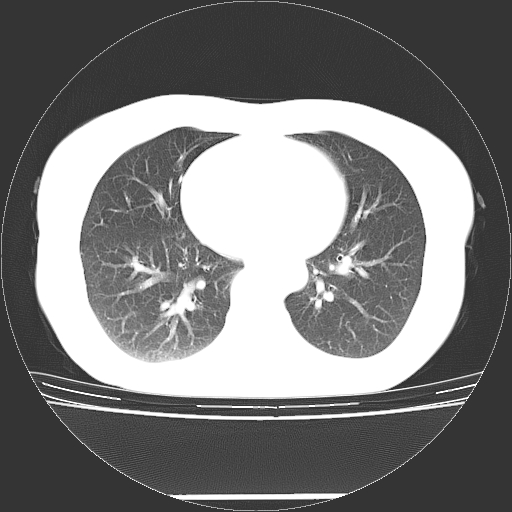

标题: CT27224:女,43岁,体检发现左肺下叶结节影。 [打印本页]

女,43岁,体检发现左肺下叶结节影。

左下肺外带胸膜下见孤立实性均匀密度结节影,边缘光整,增强呈渐进性强化,病灶吴分叶征及毛刺征象;支持硬化性血管瘤。

左肺下叶基底段圆形结节,多考虑:错构瘤>硬化性血瘤>炎症假瘤>周围性肺癌!期待结果!

左肺下叶外侧基底段圆形结节,多考虑:错构瘤>硬化性血瘤>炎症假瘤>周围性肺癌!期待结果!

良性结节,有钙化,强化不明显,考虑软骨性错构瘤。

左肺下叶外基底段良性结节(错构瘤?)。